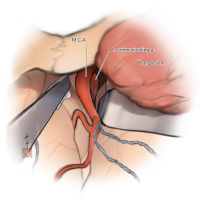

監修:谷川 緑野 / 札幌禎心会病院脳卒中センター

監修:太田 仲郎

監修:永田 雄一